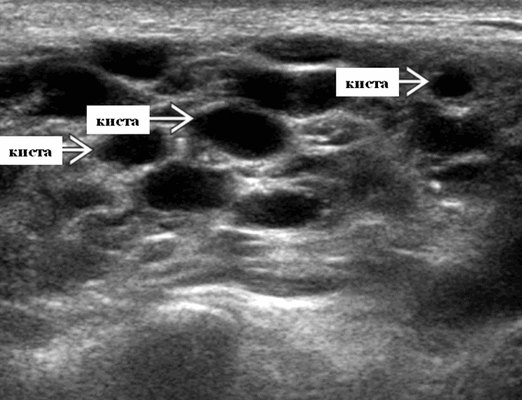

- Серошкальное УЗИ. Спектр сонографических находок от простых кист до смешанных и солидных образований. Кистозные, смешанные и солидные поражения могут возникать одновременно в околоушных железах. Кистозные поражения (кисты ДЛК). Хорошо очерченная киста, разного размера, от анэхогенной до гипоэхогенной структуры с задним акустическим усилением. Сеть тонких перегородок ± муральные узлы. Часто встречаются внутренние эхо, которые могут быть мобильными. Сотовидная внешность паренхимы околоушной железы, когда она диффузно изменена з а счет кист. Смешанные поражения (ДЛП). Границы могут быть плохо очерченными, разного размера. Структура преимущественно гипоэхогенная, железы могут быть неоднородными. Без заднего акустического усиления. Солидные поражения (околоушная лимфаденопатия). Множественные овальные / круглые, гипоэхогенные, внутрипаротидные лимфоузлы на УЗИ. Четкий корковый слой ± сохранная корневая архитектура. Сопутствующая реактивная шейная лимфаденопатия

Практически во всех случаях дифференцировали лимфатический узел Кютнера (югулодигастральный), расположенный на границе средней и верхней трети шеи. Выявляемые лимфатические узлы имели размеры от 0,5 х 0,2 см до 2,3 х 0,8 см. УЗ-оценку производили после полипозиционного осмотра и нахождения самой длинной горизонтальной оси, что и принимали за максимальный поперечный диаметр. Большая часть лимфатических узлов (187) имели овальную форму с соотношением поперечного/переднезаднего более 1 (рис. 1 - 3). Тенденцию к округлению имели 30 лимфатических узлов, соотношение поперечного/переднезаднего приближалось к 1.

Мы установили, что, как правило, более округлая конфигурация лимфатического узла при его размерах, превышавших 10 мм, сопровождалась небольшими болевыми ощущениями, и более выраженной простудной (воспалительного характера) симптоматикой. Лимфатические узлы менее 10 мм чаще всего плохо пальпировались, либо вообще не выявлялись пальпаторно. Во всех случаях эхографически хорошо дифференцировался гипоэхогенный кортикальный слой и широкое, средней или чуть ниже средней эхогенности изображение области ворот лимфатических узлов. Четкость дифференциации составных частей лимфатического узла была снижена при размерах менее 5 мм. Мы отмечали различную толщину гипоэхогенного изображения области коры лимфатического узла: от очень широкой - при выраженности или прогрессировании воспалительного процесса, до узкой - на фоне положительной динамики.